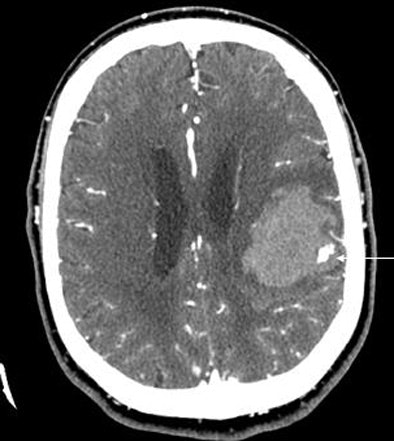

| A 64-year-old man presented with acute onset of right arm weakness and aphasia. The patient underwent CT/CTA. Neuroradiologists were initially concerned the CT findings (arrows, above and below) represented an AV malformation. Further examination left them unable to track the contrast through any vascular distribution, however, and they hypothesized that the findings represented contrast extravasation. Two hours later the patient suffered significant clinical deterioration; repeat head CT showed hematoma expansion. Direct angiography showed no AVM, and subsequent surgical excision found only hematoma and no vascular malformation. In 104 patients, lack of a spot sign had a 98% negative predictive value for identifying patients who would not have hematoma expansion at follow-up. Image courtesy of Dr. Joshua Goldstein. |